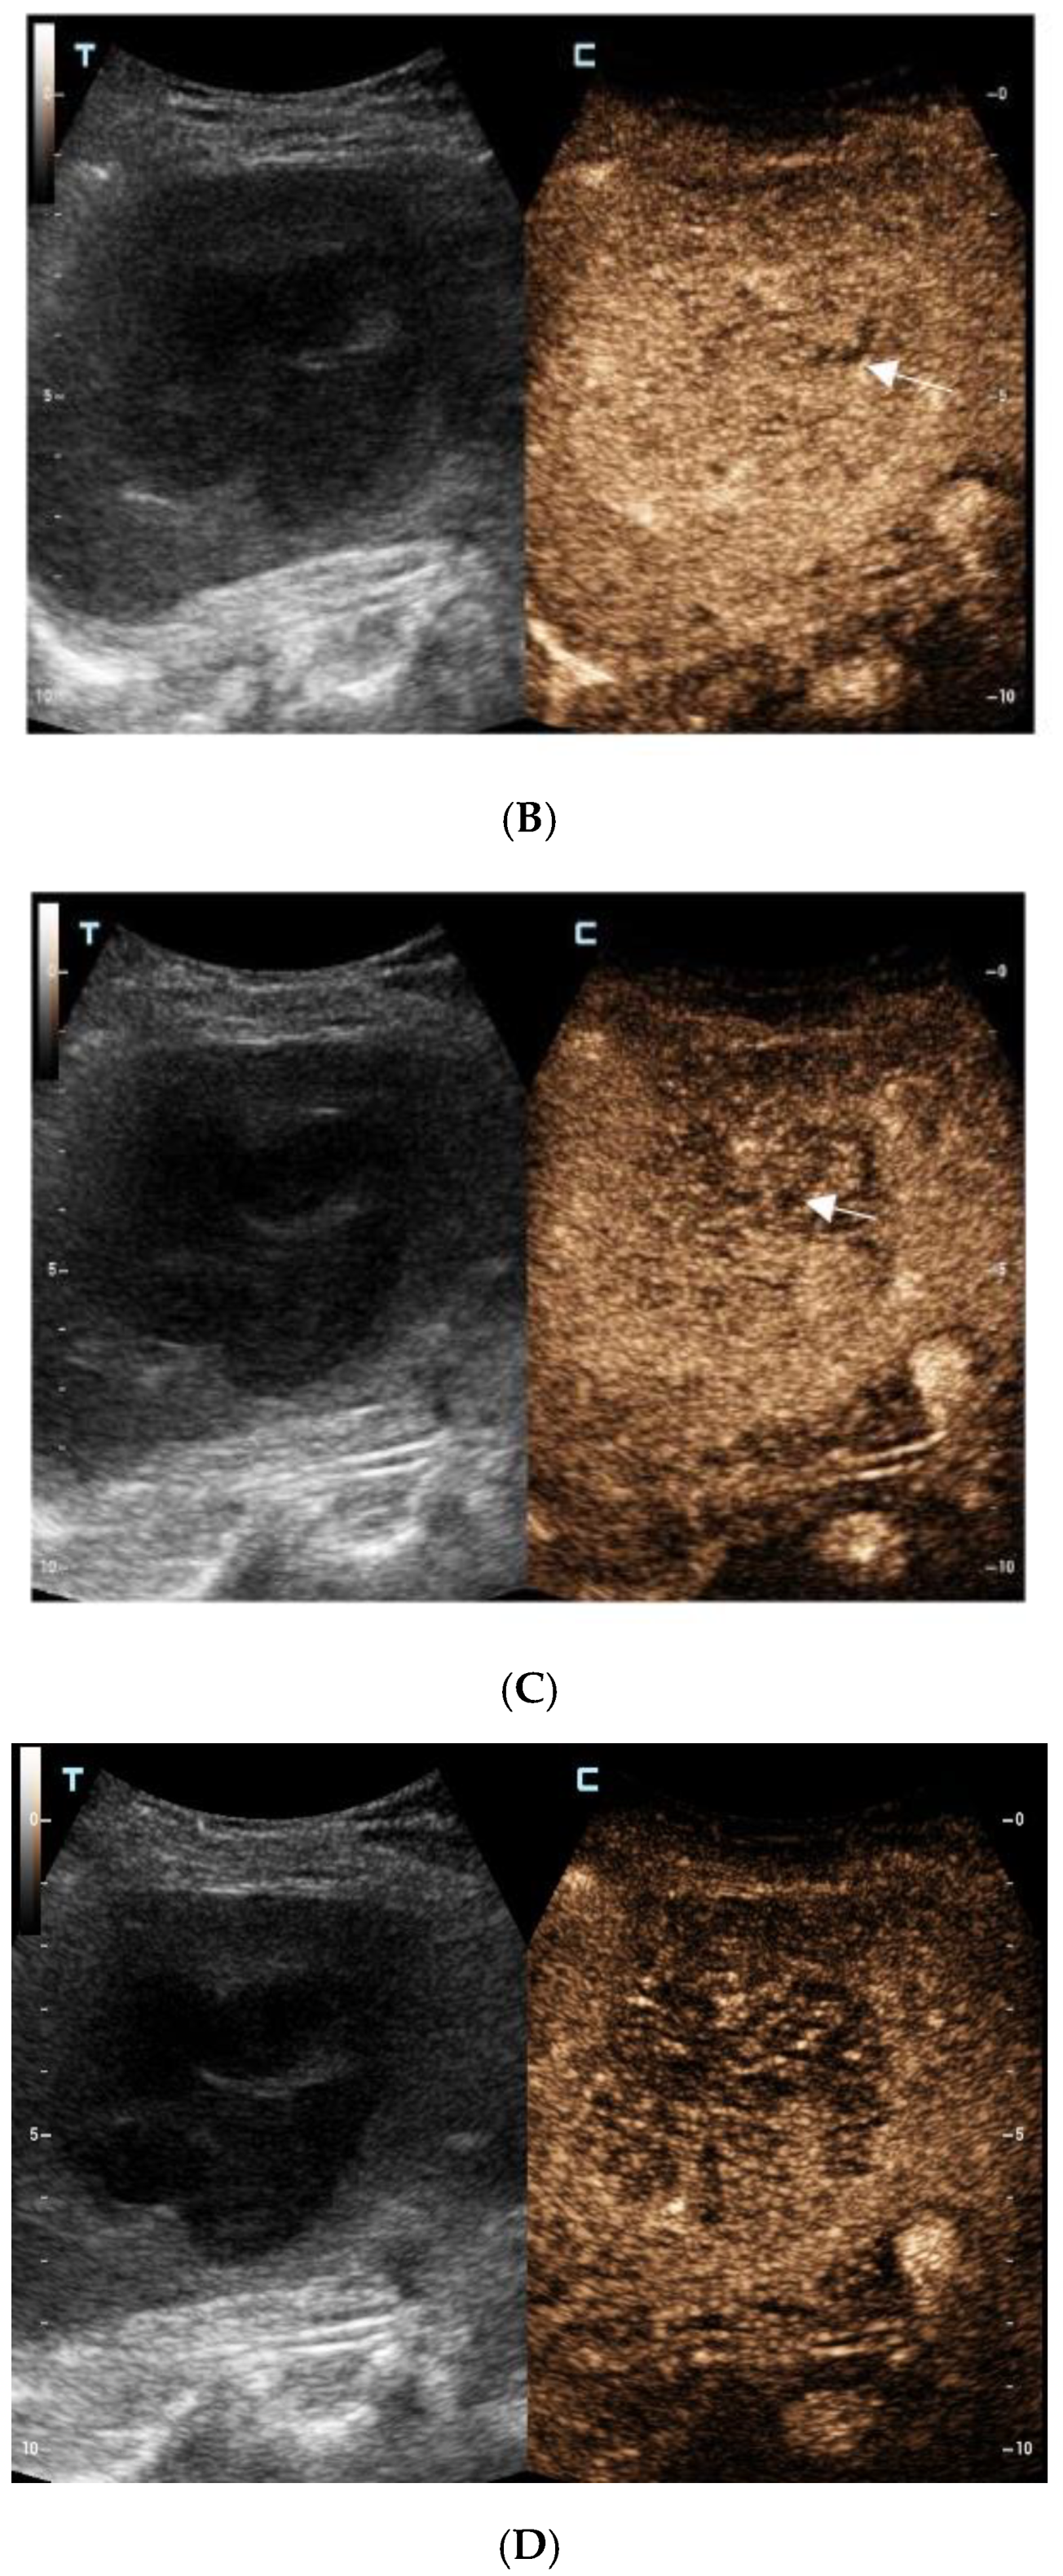

For further diagnosis, abdominal magnetic resonance imaging (MRI) was performed. The hepatic nodule was slight hyperintense on unenhanced T1WI (A). On T2WI, it was markedly hyperintense (B). On the contrast-enhanced scan, the hepatic lesion presented non-rim hyperenhancement in the arterial phase (C), but it was hypointense in the portal venous and late phases (D). The capsule-like hyperenhancement area was also observed in the late phase ((E), arrow). According to the American College of Radiology Liver Imaging Reporting and Data System (LI-RADS), it was classified as LR-5 [1].